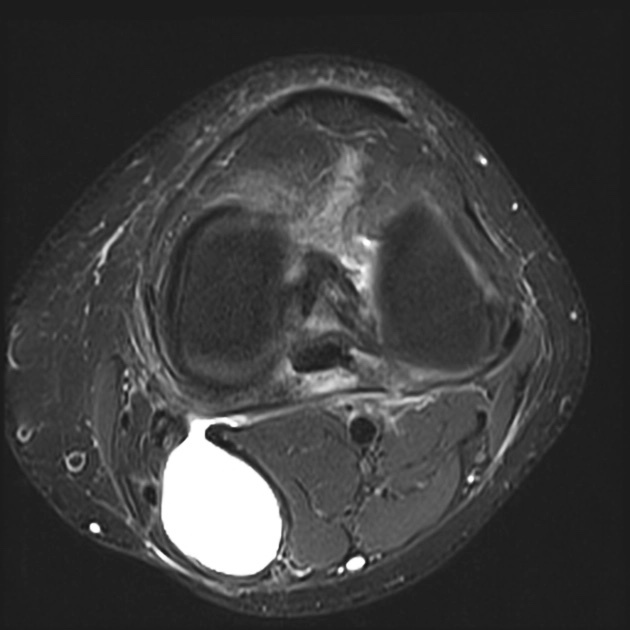

УЗИ - самый доступный и безопасный метод, саму кисту прекрасно видно.

МРТ, когда нужно заглянуть дальше, например, чтобы исключить повреждение заднего рога мениска или крестообразных связок - такие глубоко залегающие структуры по УЗИ не видно.

Иногда в полости кисты можно найти какие-нибудь образования, которые мигрировали из полости сустава (кальцинаты, костные тела, хрящевые тела, костно-хрящевые).